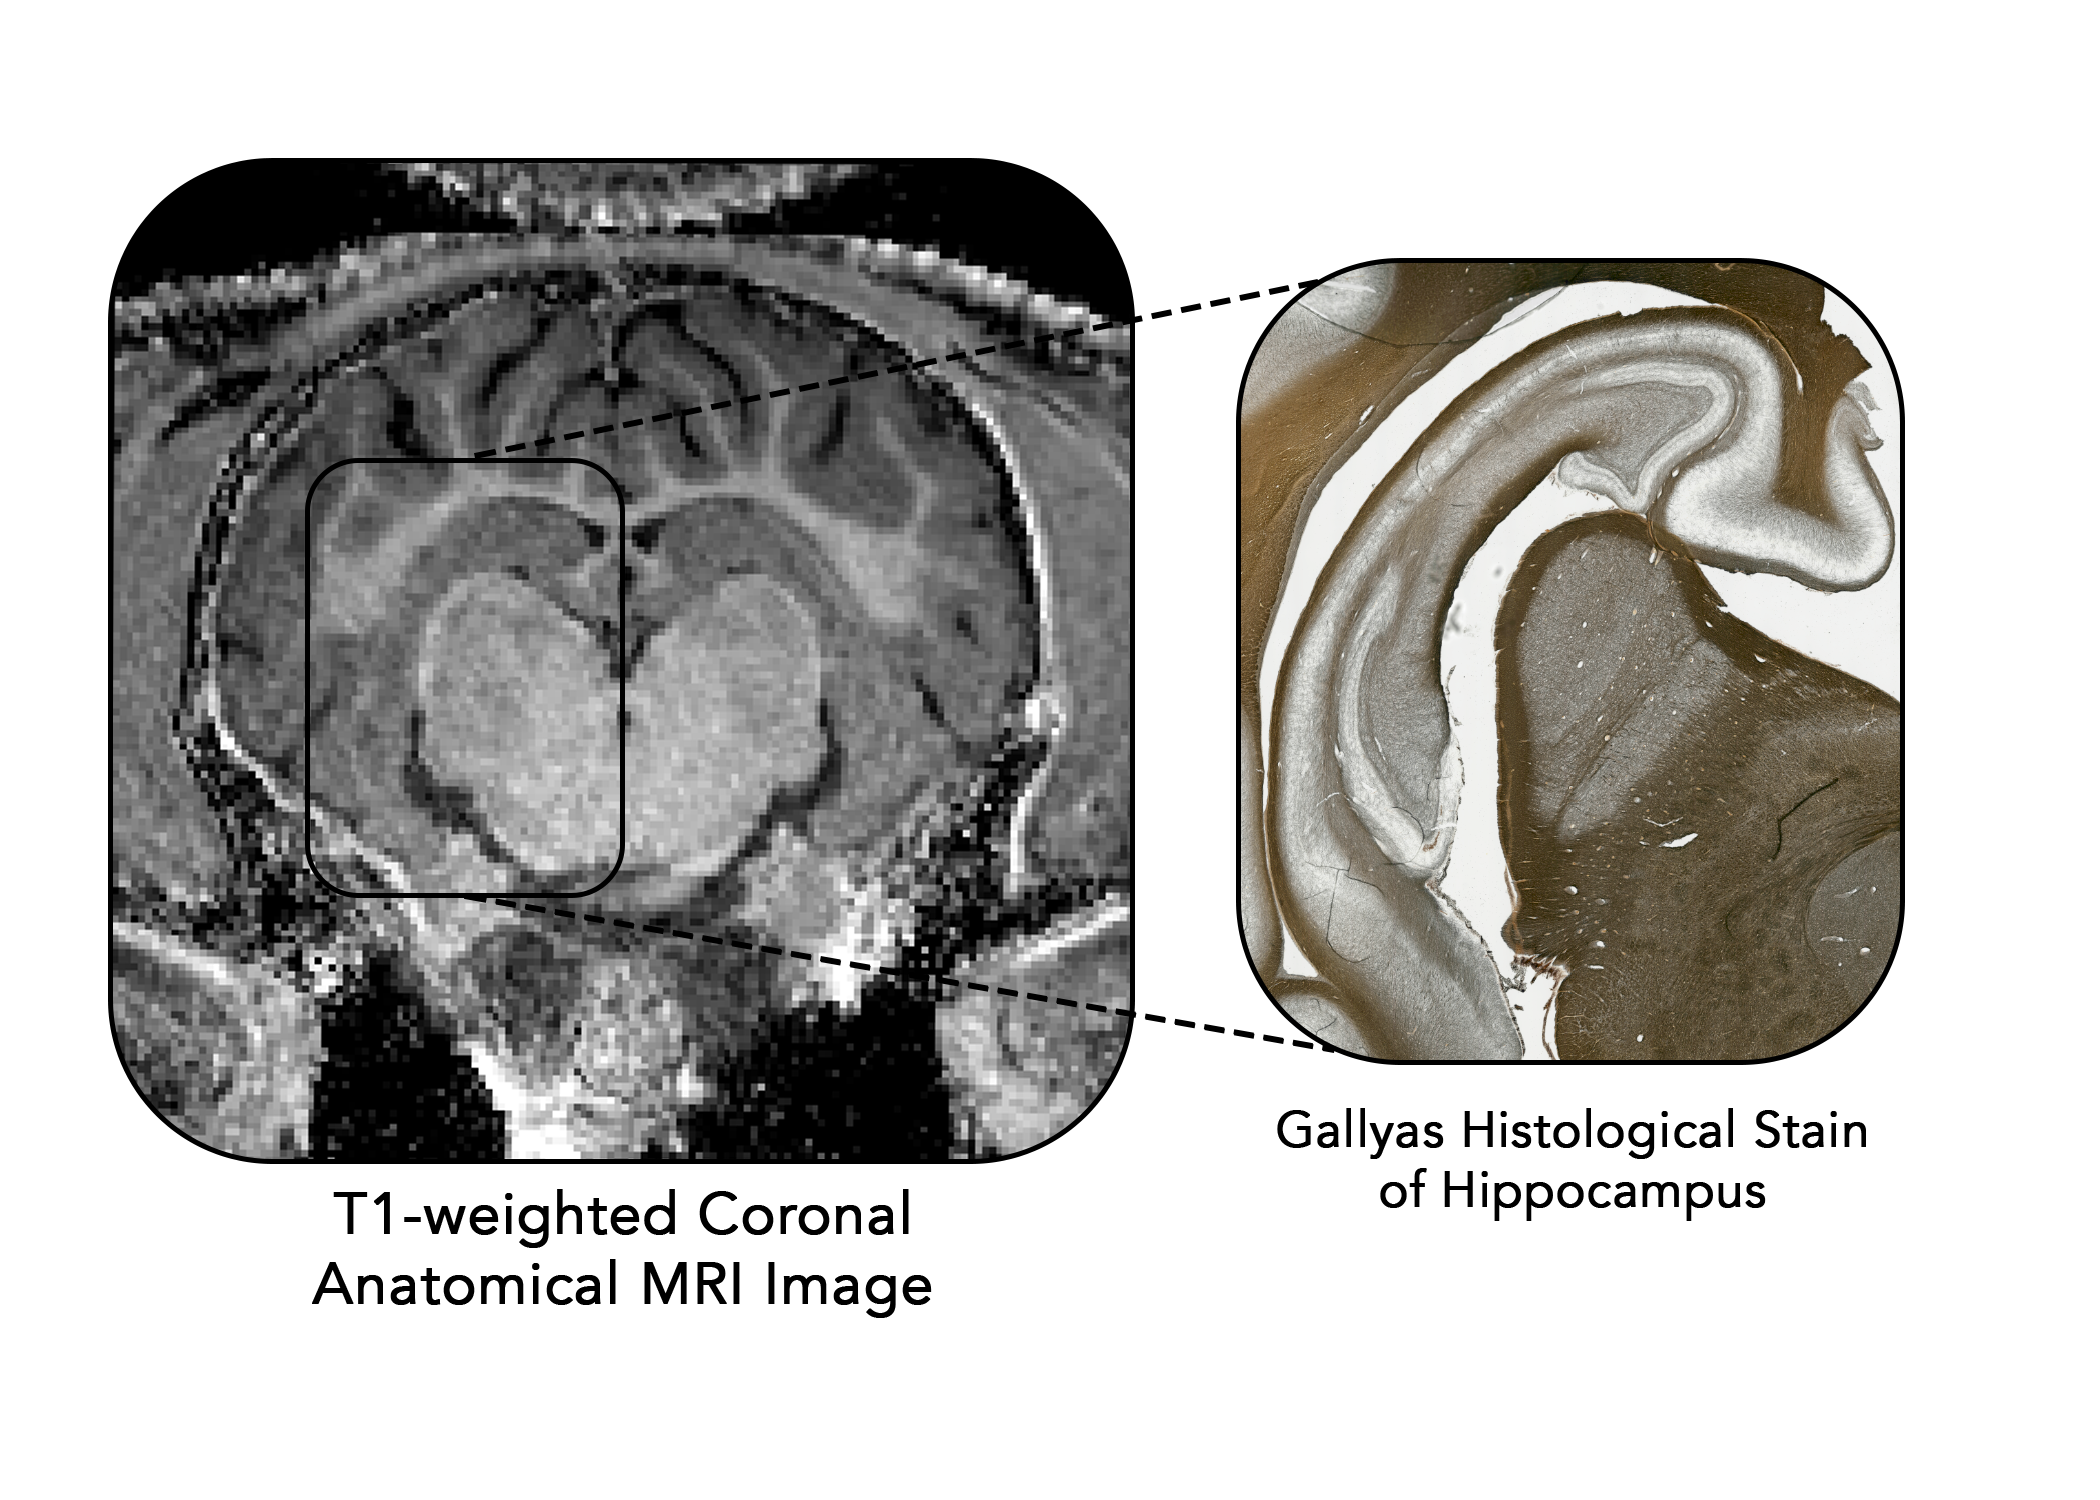

Using various histological measures, we can assess the microstructure of different regions.

Our lab has particularly been interested in the hippocampus - a mixed gray matter and white matter region important for memory function.

Using different stains, we can obtain different microstructural information about the tissue.

Individual myelin fibers are darkly stained with this method allowing quantification of myelin density within a tissue.